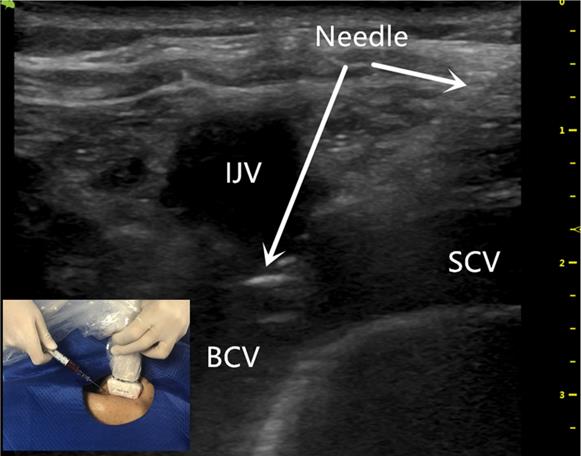

The US probe was run down the IJV (Figure 1) to the top of the sternoclavicular joint to obtain a longitudinal view of the BCV. The puncture site was locally anesthetized with 1% lidocaine. With the guidance of the US probe (the in-plane technique), the needle was advanced once the BCV was visualized on the US screen (Figure 2). After successful puncture, the guide wire, sheath, and catheter were entered sequentially.

Figure 2

The ultrasound-guided successful puncture of the BCV needle insertion (white arrow) using the BCV longitudinal view, in-plane approach. BCV indicates the brachiocephalic vein; IJV indicates the internal jugular vein; SCV indicates the subclavian vein.